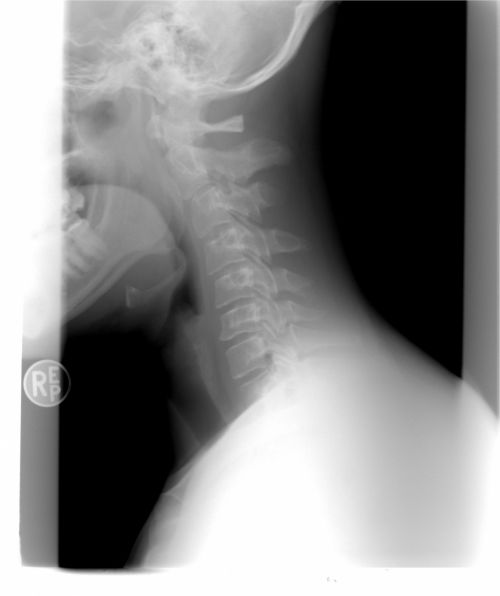

Спондилез в области шеи называется шейным спондилезом. Данный износ может наблюдаться и в других сегментах позвоночника, включая поясничную область или нижнюю часть спины.

Цервикальный спондилез может зажать нерв для шеи так, что это вызывает странное ощущение - этот тип проблемы с шеей называется радикулопатия. При этом условии, мышца шеи может чувствовать себя онемевшей или слабой.

Симптомы будут различаться в зависимости от затрагиваемой части позвоночника. Спондилез в нижней части спины может вызывать симптомы, которые влияют на то, как человек сидит. С проблемой в нижнем отделе позвоночника, мышечной слабостью и другими проблемами, связанными с нервом, будут страдать ноги, а не шея или руки. На шею и руки влияет более распространенный случай спондилеза в области шеи.

Хирурги будут делать любую операцию, соответствующую точной проблеме с позвоночником. Это будет запланировано против общих клинических признаков и результатов сканирования, таких как рентгеновские снимки.